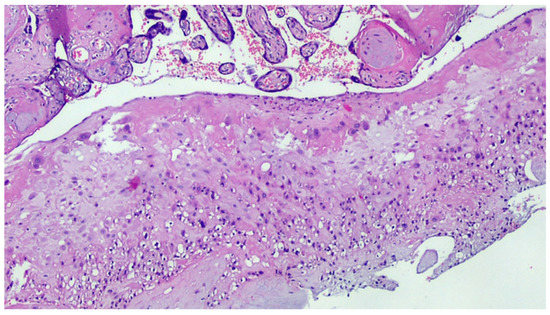

Figure 1.

COVID-19-positive mother placenta. Terminal chorionic villi with poor vascular component (distal hypoplasia of the villi due to early maternal malperfusion) with increased syncytial nodes. Some villi show a deposition of fibrin in the intervillar space with progressive reduction of the villi (H&E, Hematoxylin and Eosin, 100×).

Figure 4.

Deciduitis with large foci of necrosis and massive infiltration of mainly granulocytic inflammatory elements (acute deciduous, H&E, 200×) in the placenta of a COVID-positive mother.